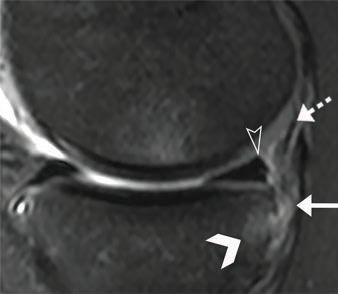

Sharpen your MRI skills with this review of posteromedial meniscocapsular ramp lesions: critical anatomy, pathogenesis, and key diagnostic criteria to help rads accurately recognize these common-but-missed injuries and guide orthopedic surgical planning. www.ajronline.org/doi/10.2214/...

This AJR Special Series Review offers a clear, focused look at posteromedial meniscocapsular ramp lesions.